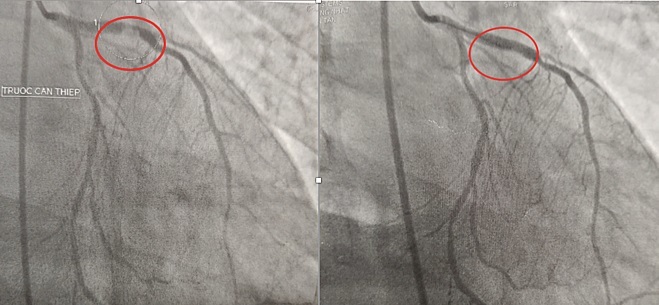

Hình ảnh bên trái trước khi can thiệp và phải là sau khi can thiệp mạch vành của bệnh nhân. Ảnh: L.P

Tiếp nối, bác sĩ tim mạch tiến hành chụp động mạch vành, phát hiện tắc 3 nhánh. Bác sĩ nhanh chóng tiến hành can thiệp đặt một stent ở nhánh thủ phạm nhằm giải quyết tình trạng suy tim cấp. Sau khi được can thiệp tim lẫn thần kinh, bệnh nhân đã cải thiện tri giác và được rút ống thở. Hiện, bệnh nhân tỉnh táo, tiếp xúc tốt, ăn uống được.